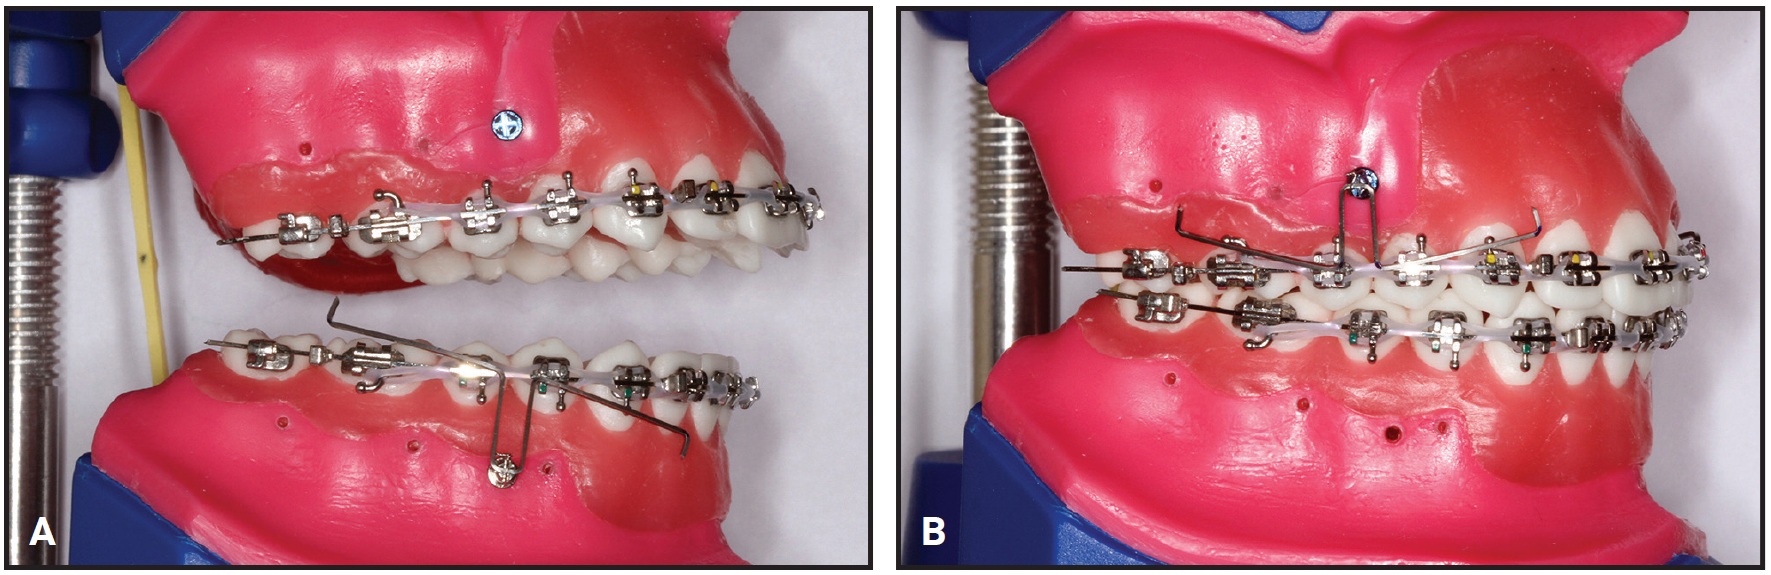

The DAVIT is fabricated by making six right-angle bends in an .017" × .025" TMA wire, resulting in a horizontal anchorage segment, two vertical extensions, and two horizontal power arms with vertical plugs at the ends (Fig. 2A). The horizontal anchorage segment is fitted into the slot of a bracket-head mini-implant, while the vertical plugs of the horizontal power arms are inserted into the vertical slots of orthodontic cross-tubes positioned between the lateral incisor and canine and the first and second molars (Fig. 2B).

Fig. 2 A. DAVIT appliance fabricated from .017" × .025" TMA* wire. B. Horizontal anchorage segment fitted to bracket-head mini-implant; vertical plugs inserted in cross-tubes positioned in anterior and posterior segments.

After seven months of treatment, the initial alignment was complete. A bracket-head mini-implant (1.5mm × 8mm, with a 1mm transmucosal collar) was inserted on each side between the upper premolars to provide skeletal anchorage for the DAVIT device (Fig. 7). The right and left mini-implants had counterclockwise and clockwise thread directions, respectively, to prevent screw failure due to the rotational force load.35 The posterior power arms of the DAVIT were activated above the .019" × .025" alignment archwire to produce a posterior intrusive force of about 300g per side. The anterior power arms were activated below the archwire to produce an anterior extrusive force of about 150g on each side, for a total 300g of anterior extrusive force. The horizontal anchorage segments of the DAVIT were tied into the mini-implant bracket slots with .008" stainless steel ligature wire. Finally, the activated vertical plugs at the ends of the horizontal power arms were inserted into the vertical slots of orthodontic cross-tubes positioned between the lateral incisor and canine and between the second premolar and first molar on each side of the maxillary arch.

Fig. 7 After seven months of alignment, mini-implants inserted between upper premolars, and DAVIT appliances activated to correct open bite by posterior intrusion and anterior extrusion.